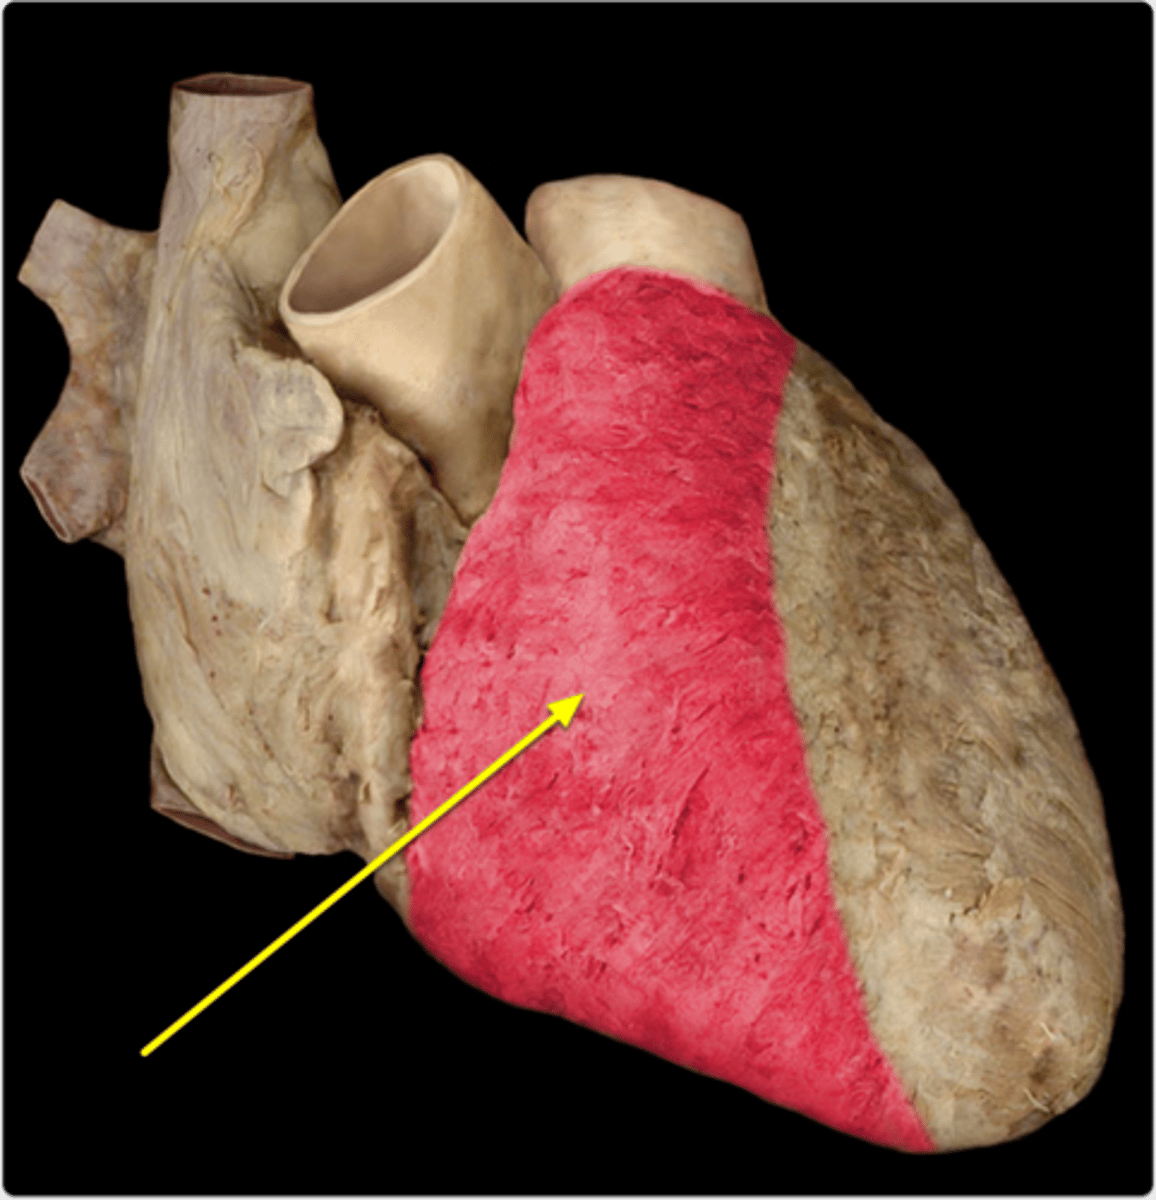

costal surface (of heart)

the forward-facing surface located directly behind the sternum and the costal cartilages